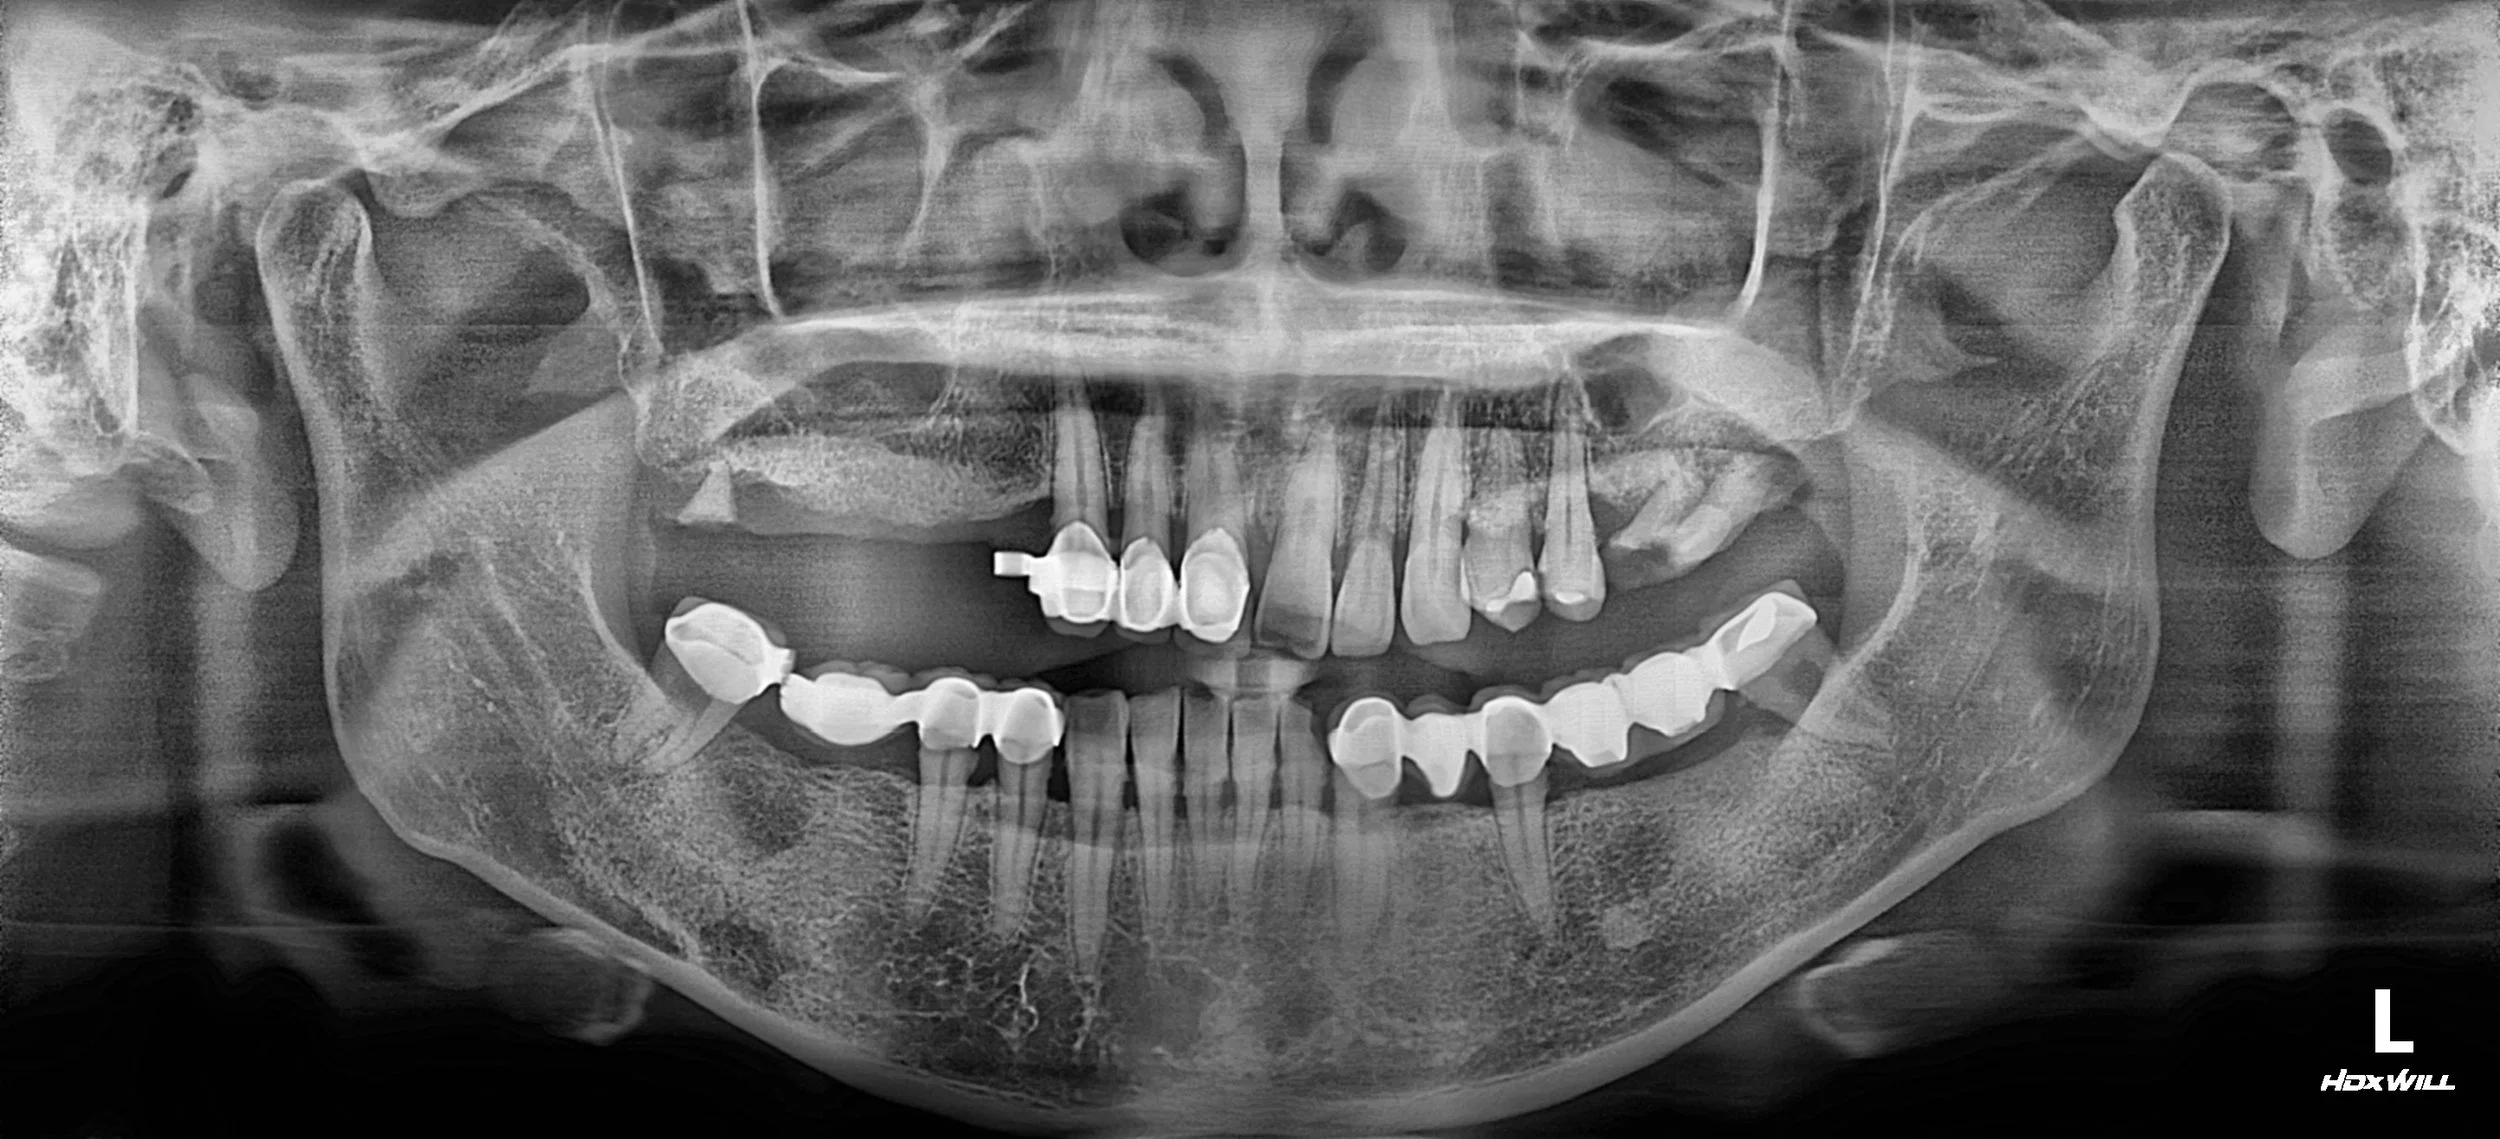

OPG - BEFORE

The patient had discontinued use of an ill-fitting removable denture and relied on unilateral mastication over an extended period.

As a result, the contralateral dentition deteriorated, leading to progressive occlusal collapse and aesthetic concerns.

Despite the compromised occlusion, the patient wished to preserve an existing fixed bridge for financial reasons.